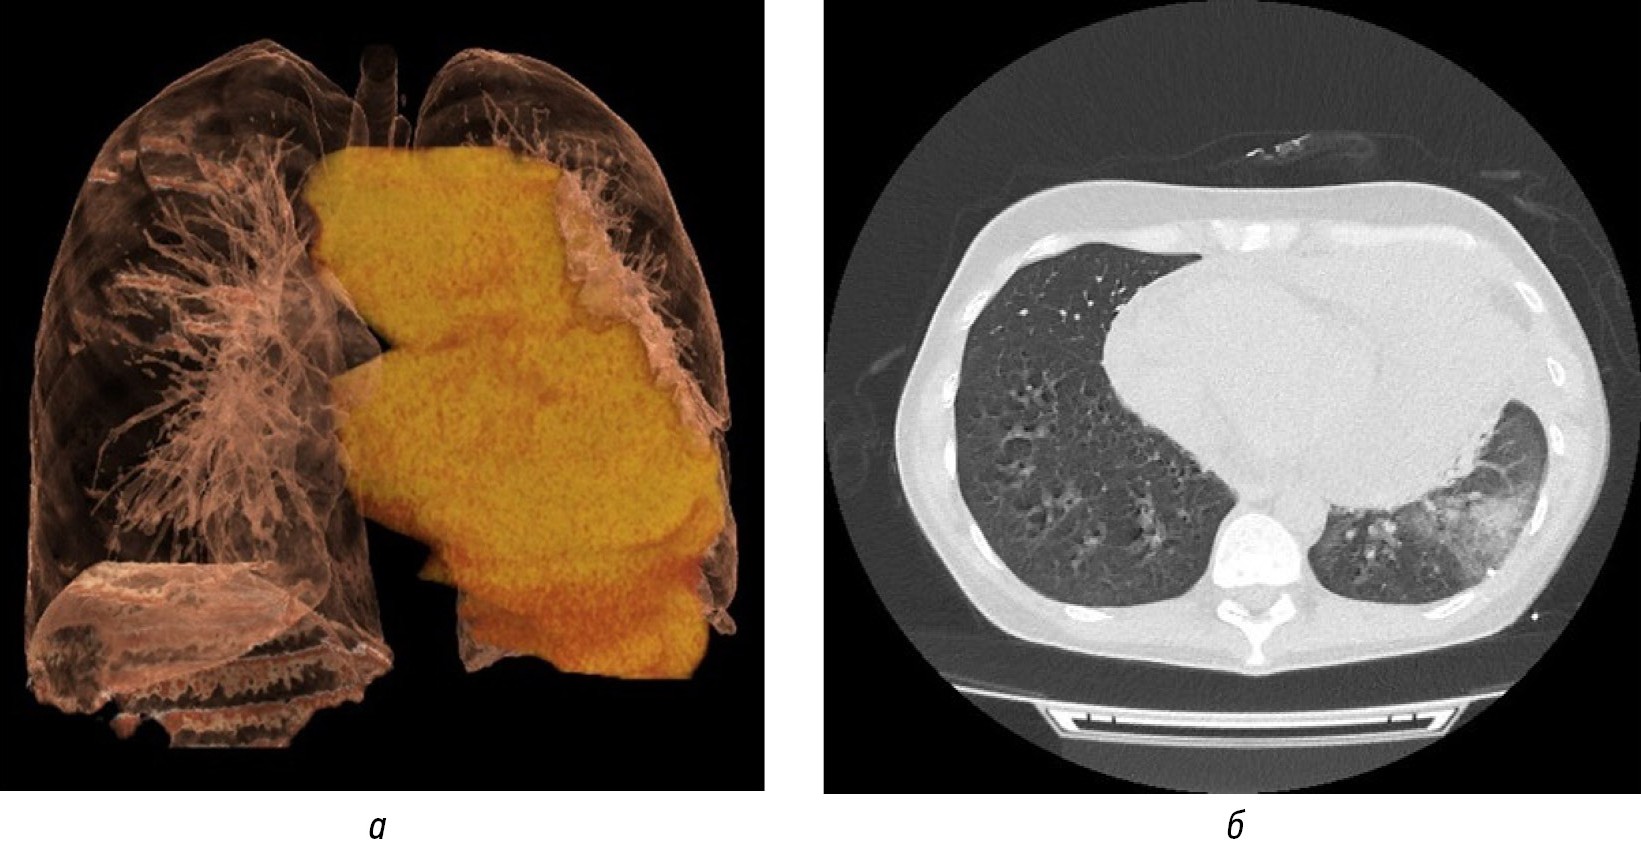

При лабораторном обследовании пациентки по данным клинического анализа крови выявлена гипохромная микроцитарная анемия (гемоглобин 93 г/л при норме 105–115 г/л в третьем триместре беременности, MCH 24,2 пг при норме 26–33,5 пг, MCV 70 фл при норме 80–100 фл) на фоне снижения гематокрита (26,9% при норме 34,7–47,0%), а также абсолютная (0,26×109/л при норме 1,26–3,20×109/л) и относительная (4,2% при норме 19–45%) лимфопения. По результатам биохимического анализа крови обнаружена гипоальбуминемия (32,7 ЕД/л при норме 34–50 ЕД/л). По данным эхографии плевральных полостей слева отмечалась сепарация листков плевры за счёт наличия однородного анэхогенного содержимого. Учитывая нарастание одышки, провели дренирование левой плевральной полости — эвакуировано 500 мл серозной жидкости, цитологический анализ которой показал наличие крупных бластных клеток лимфоидного ряда. По данным эхокардиографии обнаружили расширение полостей левого и правого предсердий, правого желудочка, гипертрофию миокарда левого желудочка, утолщение стенок аорты, разделение листков перикарда. По результатам компьютерной томографии органов грудной клетки выявили наличие объёмного образования средостения размерами 200×150 мм с неровными бугристыми контурами и признаками компрессии трахеи и левого главного бронха, инфильтративными изменениями нижней доли левого лёгкого, явлениями левостороннего плеврального и перикардиального выпота, а также наличие образования плевры справа (рис. 1).

Рис. 1. Компьютерная томограмма органов грудной клетки с визуализацией объёмного образования средостения с компрессией сердца, аорты, трахеи и главных бронхов: а — коронарный срез в 3D-режиме; б — аксиальный срез в лёгочном режиме.